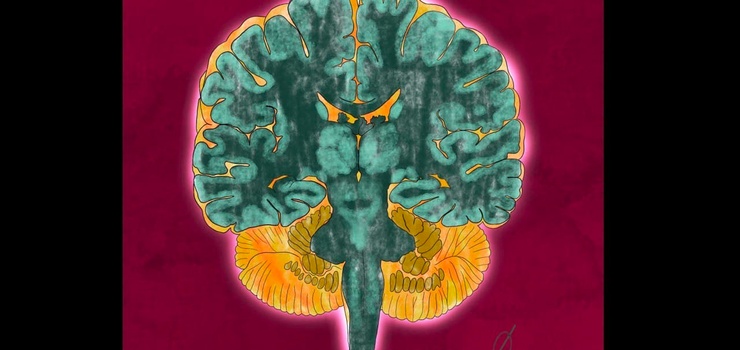

AnatomieA: Nervensystem

Ein Spatziergang um gleichzeitig sein Gehirn mit Wissen zu füllen und von der Schreibtischlernerei frei zu pusten.